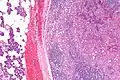

| Micrograph of an acinic cell carcinoma (right of image) and acinar glands (parotid gland - left of image). H&E stain. | |

Basophilic, bland cells similar to acinar cells. Growth pattern: solid - acinar cells, microcytic - small cystic spaces mucinous or eosinophilic, papillary-cystic - large cystic lined by epithelium, follicular - similar to thyroid tissue.

These tumors, which resemble serous acinar cells, vary in their behavior from locally aggressive to blatantly malignant.

Very high mag.